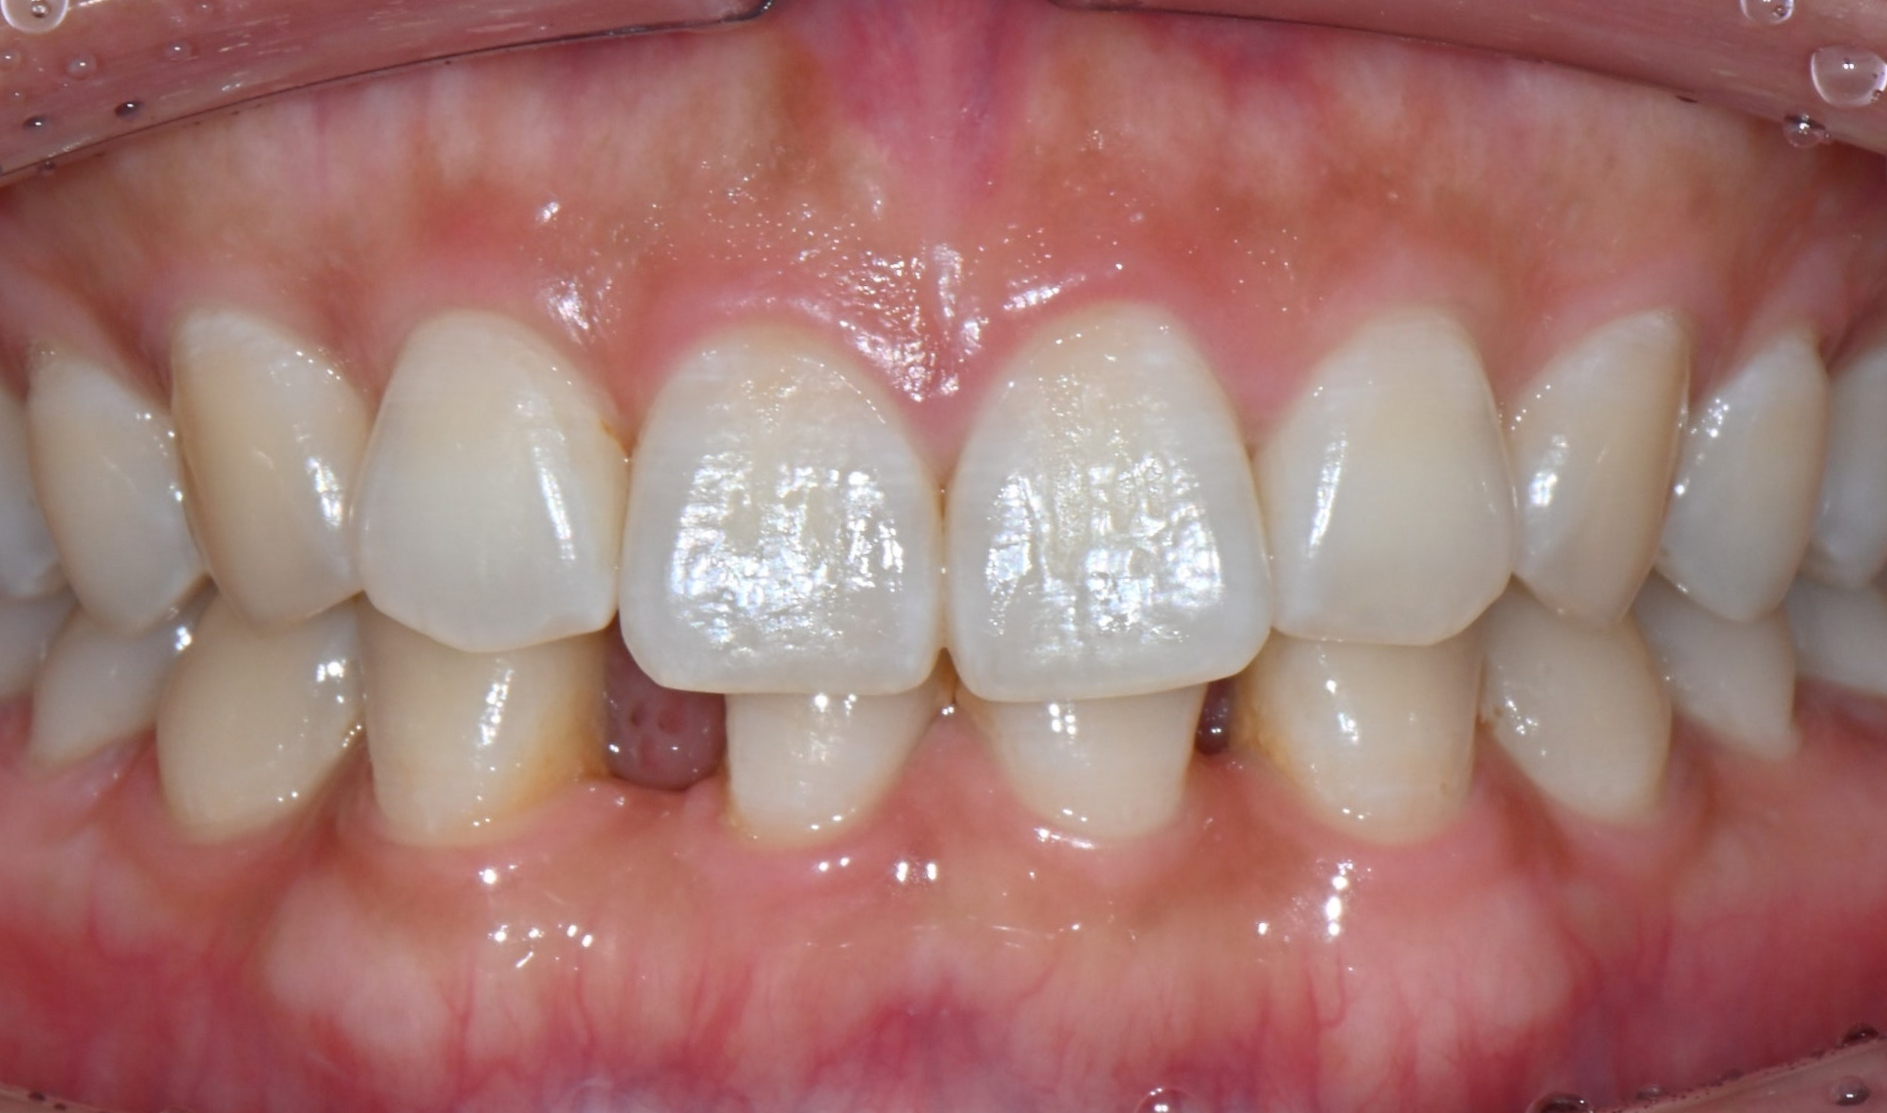

26.04.02 치료 후 모습

치료가 끝난 후,

환자분께서는 거울을 보며

한참 동안 미소를 지으셨습니다.

평생을 따라다니던 콤플렉스가

며칠 만에 해결되었기 때문입니다.